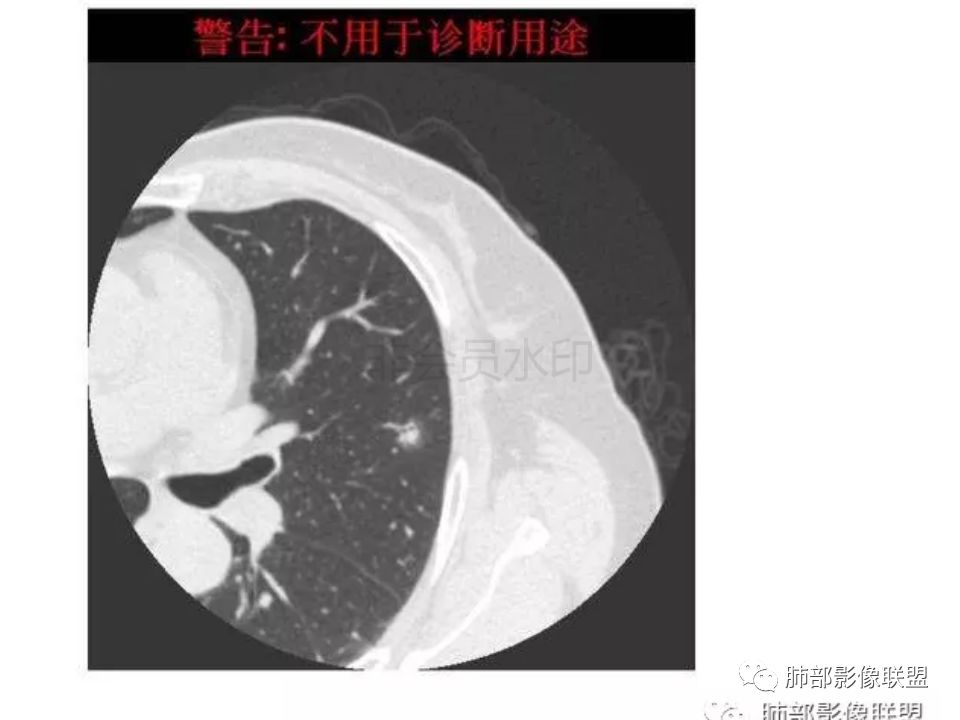

我怎么感觉支气管是通的,周围的晕又比较软,我考虑炎性病变,隐球菌可能大(如下图)

南边:首先自然是看GGO的边界如何?清楚吗?哞:边界模糊南边:其次内部的支气管如何?Coke with ice:清。可见穿行。哞:有通过,也有阻塞吧M-Imaging :进入一半南边:常规的窗宽窗位边界好像不清

也有点散南边:我觉得支气管走形自然,远端稍扩张M-Imaging :略有扩张南边:倾向于炎性宇宙星空:支持M-Imaging :腺癌的GGO,非常清晰的结果:

1.隐球菌病灶往往是实性密度结节为主伴周边边界不清楚的晕,有时可见晕内细软毛刺。

3.病灶内支气管安然无恙隐球菌病灶更加多见